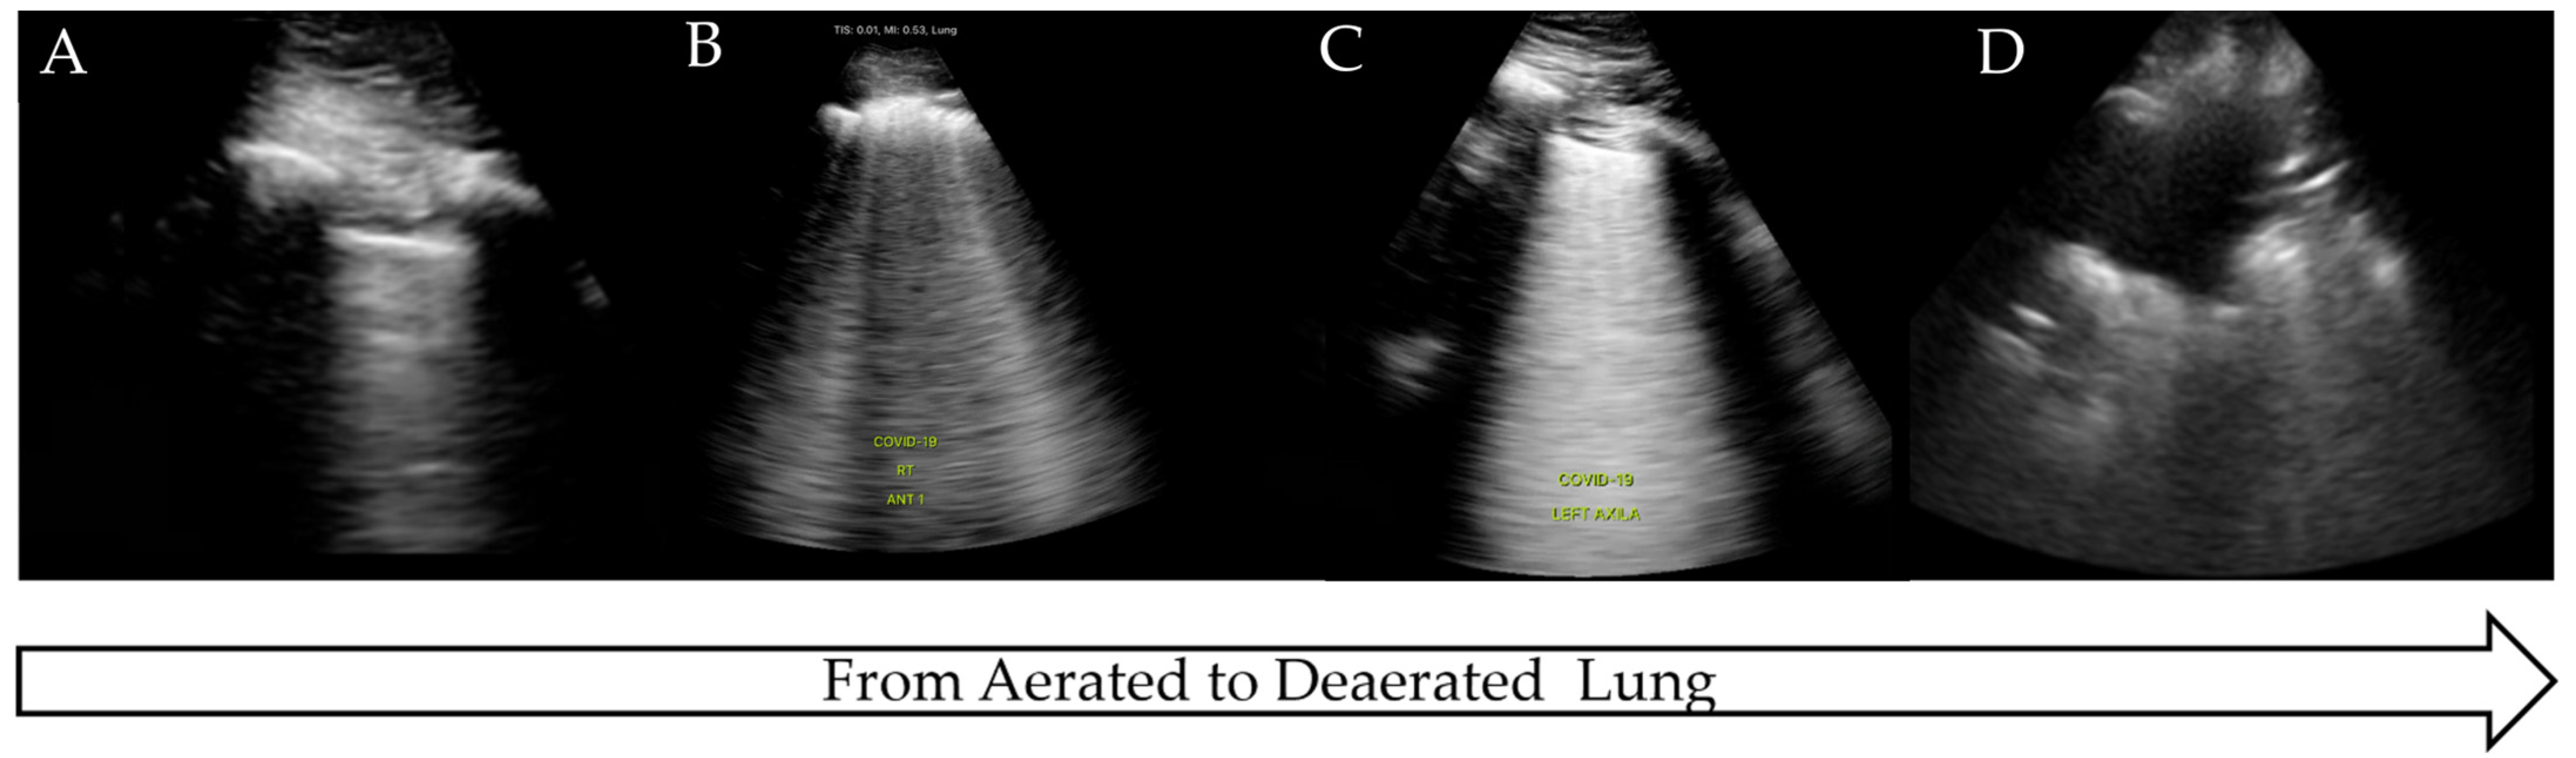

| Normal aerated lung | Movement of the pleural line with tidal ventilation Presence of A-lines (Figure 1) Maximum of 2 B-lines per image |

| Cardiogenic pulmonary oedema | Homogenous B-line distribution >3 per image (Figure 2A) Regular thin pleura Possible pleural effusions |

| Interstitial lung disease | Irregular thickened pleura in moderate to severe disease Multiple diffuse bilateral B-lines |

| ARDS/ALI | Non-homogenous B-line distribution Irregular thickened pleura Sub-pleural consolidations |